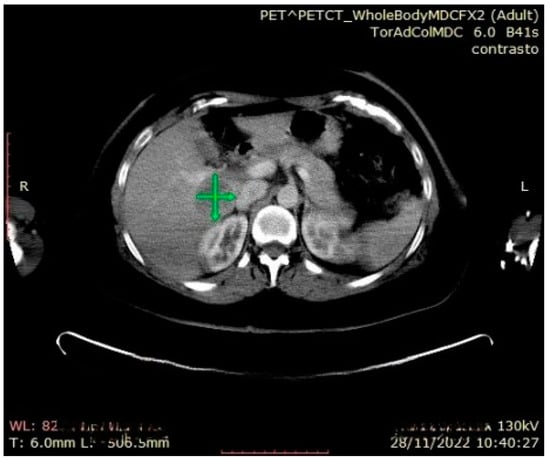

| Our Case Rep | 52 | F | R | 9 × 7 × 6 | None | Laparoscopic Adrenalectomy + Nephrectomy | CT | 12 (alive with liver metastasis) |